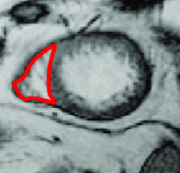

Appearance is one of the most important visual cues to distinguish between different structures in an image. Appearance is described by studying the distribution of different features such as intensity values in gray-scale images, color, and texture inside each object. In most cases, appearance models are incorporated into the data term in (2) and (7). The purpose of incorporating appearance prior is to fit the appearance distribution of the segmented objects to the distribution of objects of interest, e.g. using Gaussian mixture model (GMM) (Rother et al., 2004). In the literature, there are two ways to model the appearance: 1) adaptively learning the appearance during the segmentation procedure, and 2) knowing the appearance model prior to performing segmentation (e.g. by observing the appearance distribution of the training data). In the former case, the appearance model is learned as the segmentation is performed (Vese and Chan, 2002) (computed online). In the second case, it is assumed that the probability of each pixel belonging to particular label is known, i.e. if represents a particular set of feature values (e.g. intensity/color) associated with each image location for object, then it is assumed that is known (or pre-computed offline). This probability is usually learned and estimated from the distribution of features inside small samples of each object. Figure 9 illustrates the probability of different structures (the kidney, the tumour, and the background) in an endoscopic scene. A lower intensity in Figures 9(b-d) corresponds to higher probability.

More advanced texture features such as those based on Haar and Gabor filter banks have shown many successes in medical image segmentation (Huang et al., 2005; Malcolm et al., 2007; Santner et al., 2009). Koss et al. (1999) and Frangi et al. (1998) are two works that utilized advanced features to segment abdominal organs and to measure vesselness, respectively. In (Frangi et al., 1998), the eigenvalues of the image Hessian matrix are used for measuring the vesselness of pixels in images. This measure is used for liver vessel segmentation both in a variational framework (Freiman et al., 2009) and in a graph-based framework (Esneault et al., 2010). Statistical overlap prior is another strong appearance prior that has been proposed by Ayed et al. (2009). Their method embeds statistical information (e.g. histogram of intensities) about the overlap between the distributions within the object and the background in a variational image segmentation framework. They used the Bhattacharyya coefficient measuring the amount of overlap between two distributions, i.e. if . Ben Ayed et al. (2009) used this strong prior to segment left ventricle in MR images.